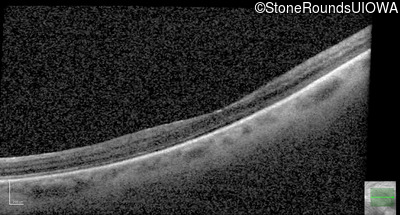

AD Familial Exudative Vitreoretinopathy (IIIE2b)

Age at visit: 32 years